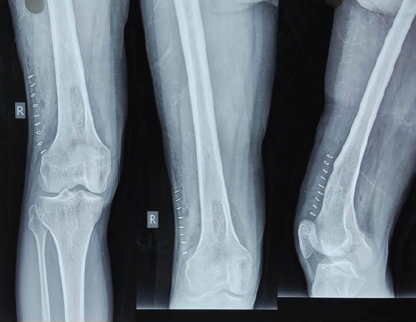

Ilizarov-Assisted Reduction of Femoral Condyle Locked in Tibial Fracture: A Case Report

Anteshwar Birajdar , Sushant Kumar , Setu Kaneria , Archit Gupta , Omkar Shinde , Sagar Gurnani